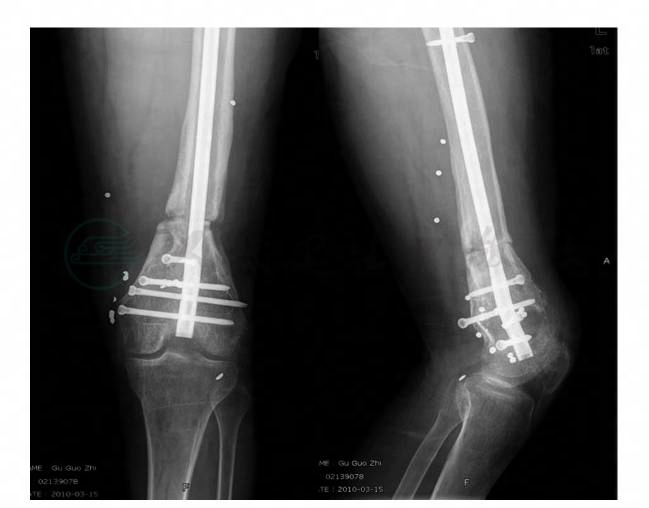

X线片显示股骨远端内翻畸形(图3)。

图3 术前X线片

术后X线片,可见股骨内翻畸形纠正,截骨端由于不在CORA,截骨端平移以纠正机械轴对线。截骨端内侧可见截骨纠正成角后的间隙,由于闭合操作,保护血运,有利于骨折愈合(图14)。术后双下肢力线X 线片证实解剖轴和机械轴位置良好(图15)。术后CT测量股骨颈前倾角、两侧前倾角相差1°、股骨无旋转畸形(图16)。